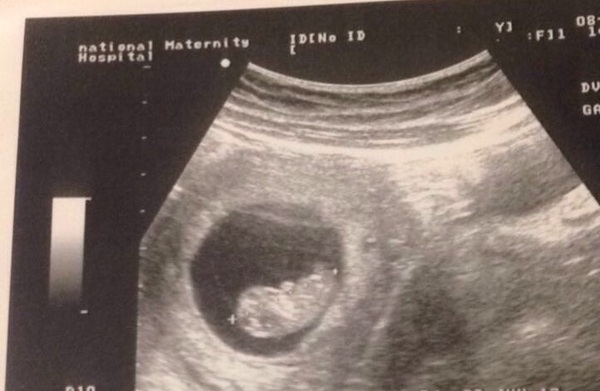

Had my 12 week scan today. So relieved it is done and everything looks good so far! I had been so worried. Feel like I can tell it's a boy too Smile what do you think?

My letter also said no need for a full bladder but the sonographer said it was good that I did have, made it much easier and we got some lovely clear pictures too.

Great scan sunflower! I think girl is possible as the nub is reasonably parallel, though if it's on or before 12 weeks it's less accurate and I'm certainly no expert. Congratulations!

Sunflower that's a great clear picture, congrats on a good scan today.

That's such a clear picture Sunflower, congratulations.

Lovely pic Sunflower :)

Lovely scan pic Sunflower!

Had another bleed today! Panic stations at the ready , straight into the hosp , baby is fine but measuring smaller than I thought was meant to be 11w5d but measuring 9w5d bit upset and that means ive another 2 weeks to panic until I hit 12 week mark , but anyways here's the bean! Have another scan to confirm that I am only 9w so if I am ️️️️il be leaving the May babies 😢😢